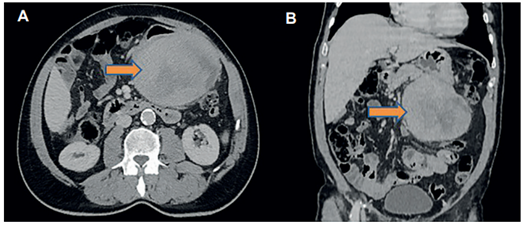

Paciente masculino de 67 años, con único antecedente de hipertensión arterial, que consultó por un cuadro clínico de dos meses de evolución de fiebre intermitente de predominio nocturno, con sensación de masa abdominal dolorosa en epigastrio; al interrogatorio negaba cambios en el hábito intestinal, náuseas, vómito o algún otro síntoma gastrointestinal. Como estudio inicial se realizó una tomografía computarizada contrastada de abdomen y pelvis en donde se describió una lesión de aspecto infiltrante tumoral primario, con compromiso de la grasa a nivel retroperitoneal en la transcavidad de los epiplones, y enfermedad diverticular (Figura 1).